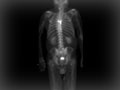

A bone scan is a test that can find damage to the bones, find cancer that has spread to the bones, and watch problems such as infection and trauma to the bones. A bone scan can often find a problem days to months earlier than a regular X-ray test.

During a bone scan, a radioactive substance called a tracer is injected into a vein in your arm. The tracer travels through your bloodstream and into your bones. Then a special camera takes pictures of the tracer in your bones.

Areas that absorb little or no amount of tracer appear as dark or "cold" spots. This could show a lack of blood supply to the bone or certain types of cancer.

Areas of fast bone growth or repair absorb more tracer and show up as bright or "hot" spots in the pictures. Hot spots may point to problems such as arthritis, a tumor, a fracture, or an infection.